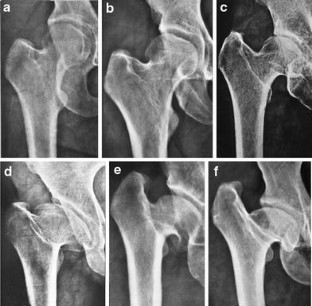

Fig. 1